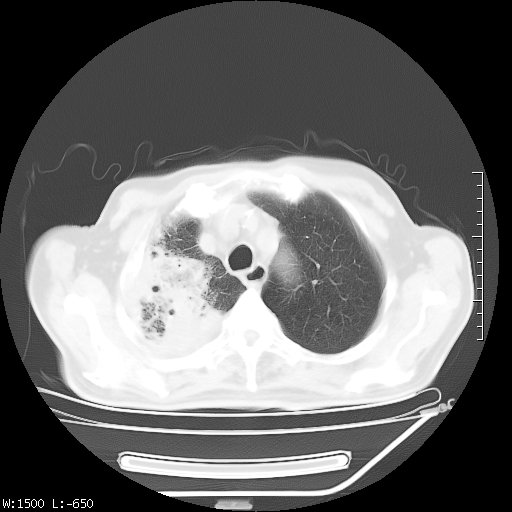

标题: CT23994:男、72、咳嗽、气短两月余,近来消瘦。 [打印本页]

标题: CT23994:男、72、咳嗽、气短两月余,近来消瘦。

tb可能性大(双肺均可见片状密度增高灶,其内可见低密度空洞)。

右上肺大片状密度增高影,与胸膜关系密切,内见低密度透亮影,胸膜下可见三角形不张影,左下肺沿支气管走形结节影,纵膈内淋巴结显示。考虑结核并疤痕性不张可能性大,建议穿刺活检,排除肺泡癌。